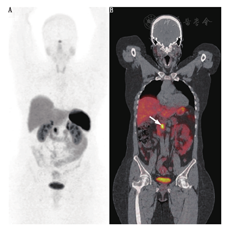

结合PET/CT的自身优势(更高的空间分辨率和灵敏度)并通过改良药理特性,将能检测较小病变或中度SSTR表达的病变,提高诊断的灵敏度和准确性(图1和图2)。

68Ga-肽PET显像在非胰腺和胰腺NETs有类似的作用(图1,图2,图3)。68Ga-肽PET显像对1型多发性内分泌腺瘤也很灵敏。在19例1型多发性内分泌腺瘤患者中进行68Ga-DOTATOC与111In-喷曲肽及增强CT的对比研究,结果显示68Ga-DOTATATE检出NETs的灵敏度为76%,111In-喷曲肽为20%,增强CT为60%;68Ga-DOTATOC检出胰腺肿瘤46个,111In-喷曲肽检出11个,增强CT检出37个[29]。一项前瞻性研究包括26例1型多发性内分泌腺瘤,对患者行68Ga-DOTATATE、111In-喷曲肽和增强CT,结果显示68Ga-DOTATATE PET/CT显像检出107个病灶,111In-喷曲肽SPECT/CT检出33个病灶,增强CT检出48个病灶;26例患者中8例(31%)因68Ga-DOTATATE PET/CT的结果而改变治疗计划,而111In-喷曲肽SPECT/CT或CT无阳性发现[30]。